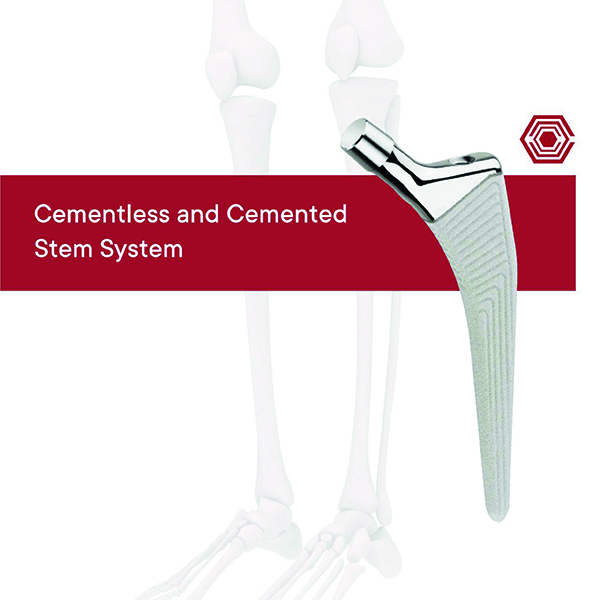

Cementless and Cemented Stem

Akif Kaya Aybek

Norm Akademi

- Surgical Technique

- Implant Types

- Instrument Types